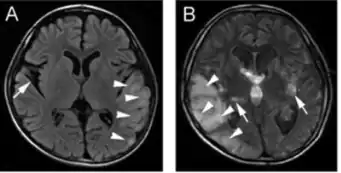

| a)Abnormal signals in the left occipital, parietal, and temporal lobes b)abnormal MRI signals shifted to the right side from previous left side; symmetrical lesions at the lenticular nuclei | |